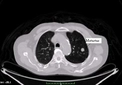

Akciğer Kanseri Metastaz Belirtileri ve Tedavisi